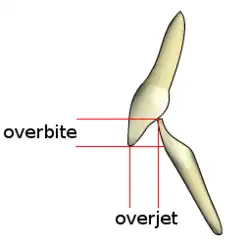

Overbite is the extent of vertical (superior-inferior) overlap of the maxillary central incisors over the mandibular central incisors,[1] measured relative to the incisal ridges.[2]

Overbite is often confused with overjet, which is the distance between the maxillary anterior teeth and the mandibular anterior teeth in the anterior-posterior axis.